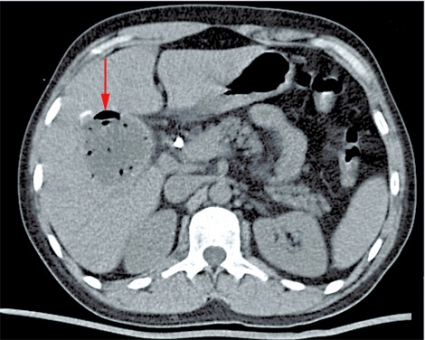

Fall 1. En 11-årig svenskfödd flicka insjuknade våren 2004 med intermittent hosta och blodtillblandat expektorat. Under sommaren utfördes en datortomografi (DT) av lungorna i Turkiet. Antibiotika gavs och föräldrarna informerades om att hon hade ekinokockos. DT på Karolinska universitetssjukhuset i Huddinge visade en oval cystisk struktur, 3,5 cm i diameter, i vänster lungas lingula. En liknande struktur påvisades i vänster underlob. I levern fanns en 5 cm stor cysta (Figur 1). Serologi var positiv avseende ekinokockos. Flickan vistades vartannat år en längre tid hos sin farfar i en by i centrala Turkiet. Detta är ett område med högendemisk förekomst av Echinococcus granulosus. Farfar är fårfarmare som slaktar hemma och ger sina hundar slaktavfall. I november 2004 fick flickan albendazol (Zentel) motsvarande 14 mg/kg/dag uppdelat på två doser. Ny DT efter fyra månader visade att cystorna i lungan minskat kraftigt i storlek. Efter ett års behandling hade de nästan helt försvunnit. Albendazol gavs i 18 månader. Ultraljud fyra år senare visade att cystan i levern minskat till 2,7 cm, och den bedömdes som inaktiv (CE4).

Fall 2. En 34-årig man från Tunisien sökte vård för buksmärta och hög feber. Patienten var ikterisk och visade tecken till gallstas. Antibiotikabehandling inleddes då den kliniska bilden talade för kolangit. Utredning med ultraljud och DT påvisade två cystiska förändringar i levern (5 respektive 6 cm stora), båda såg ut som ekinokockcystor. Blodprov visade stegrat CRP och eosinofili. Serologisk diagnostik bekräftade diagnosen. Gallvägarna avlastades med stentning via endoskopisk retrograd kolangiopankreatografi (ERCP) på grund av en intrahepatisk striktur (Figur 2). Behandlingen förbättrade initialt kolangiten, men patienten fick flera recidiv.